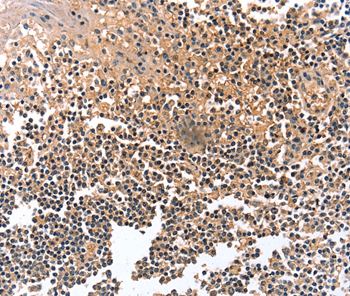

Immunohistochemical analysis of paraffin-embedded Human tonsil tissue using #36908 at dilution 1/12.

应用详情:Immunohistochemistry: 1:10-1:50